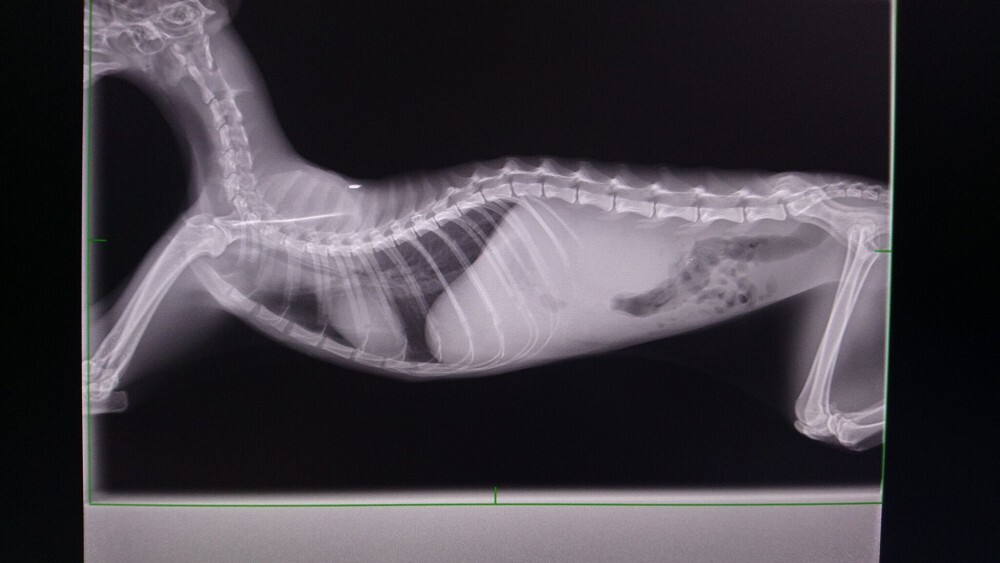

經醫師檢查發現瘦瘦有中度貧血.白血球極度偏高.黃疸.肝指數輕微偏高

也是愛滋感染的貓咪

超音波檢查發現腎腫大且大部分病灶都在腎臟皮質處.有少量腹水動物近況說明: 住院治療前醫師就有說貓咪狀況不樂觀